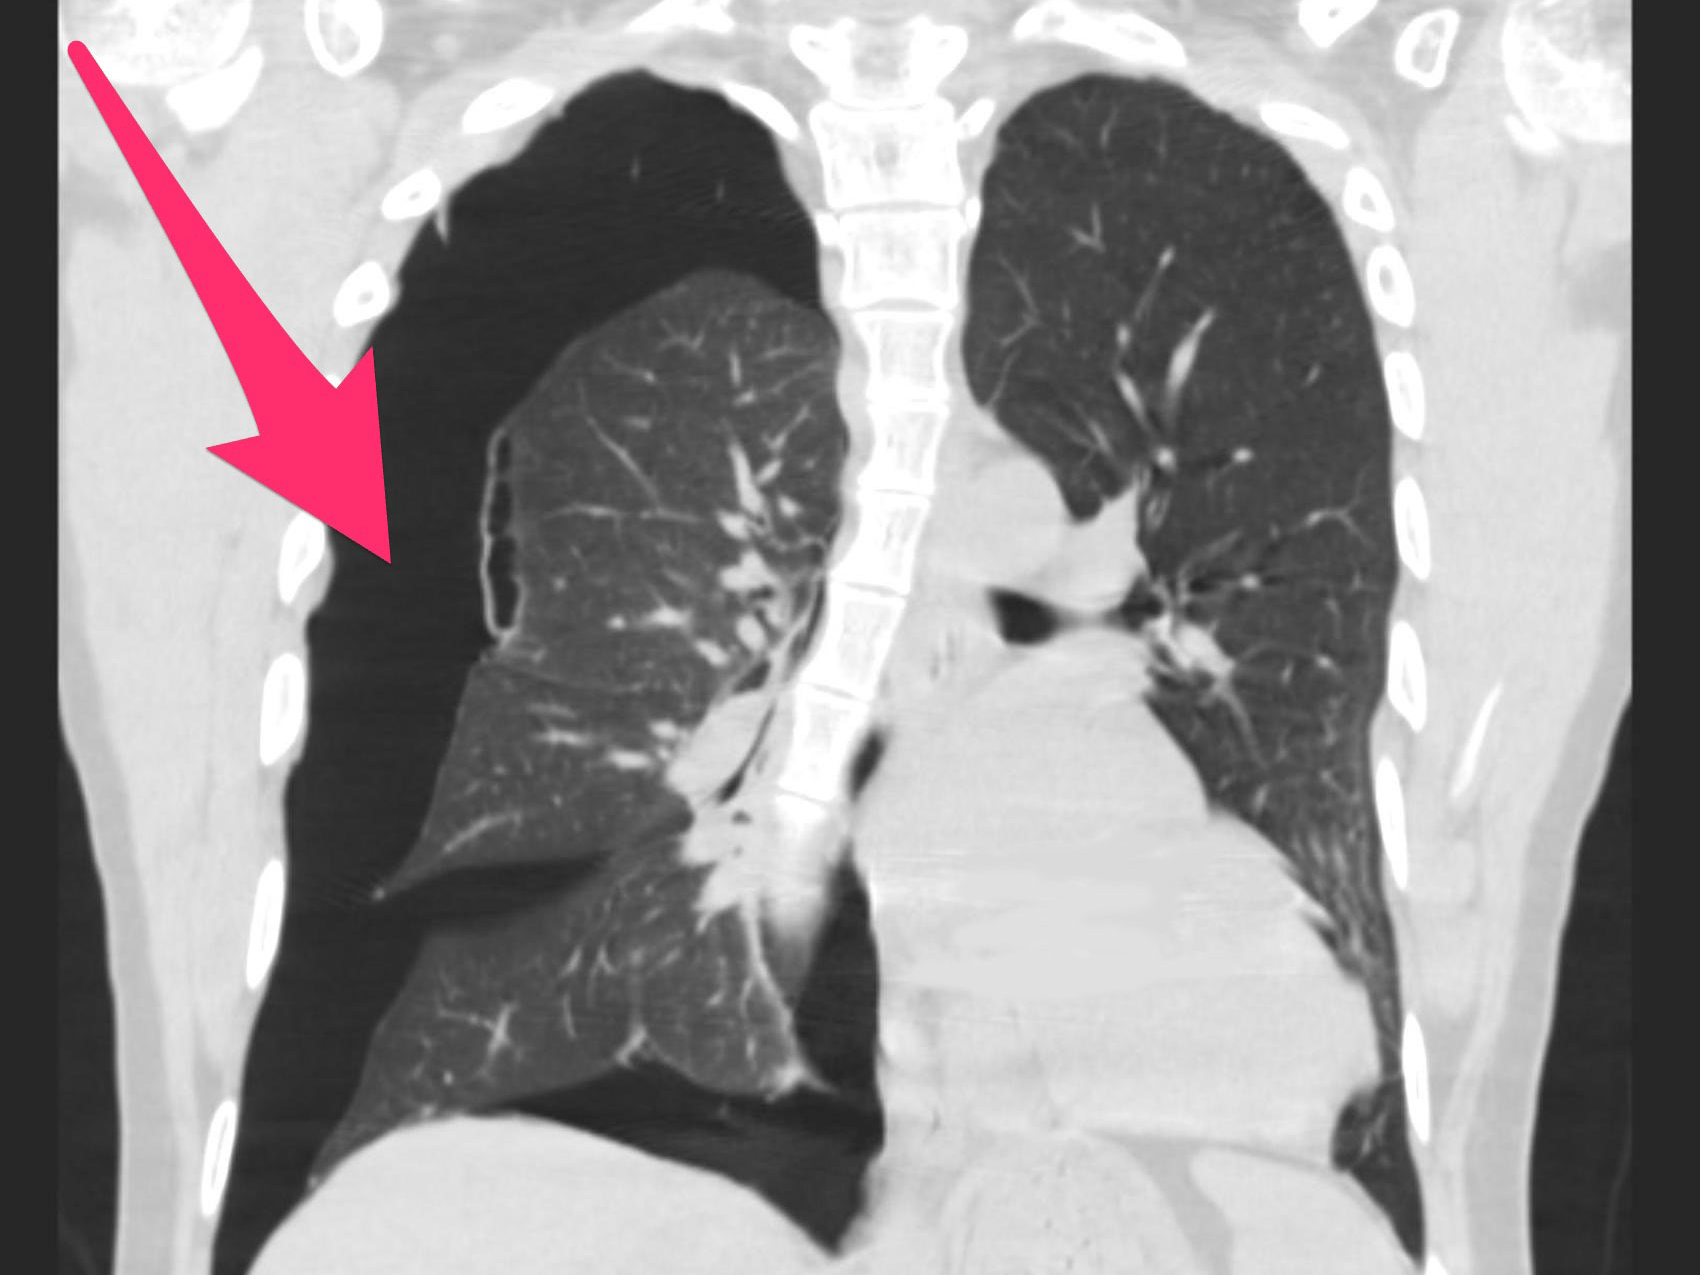

Pneumothorax (collapsed lung) Causes, symptoms, and treatment Collapsed Lung Recovery After Surgery  A pneumothorax can be a complete lung collapse or a collapse of only a portion of the lung. A lung may collapse after lung surgery or another medical procedure. You may need surgery if you don’t respond to other treatments or have:. A pneumothorax can be caused by a blunt. Your healthcare provider will give you a pathway with goals. Collapsed Lung Recovery After Surgery.